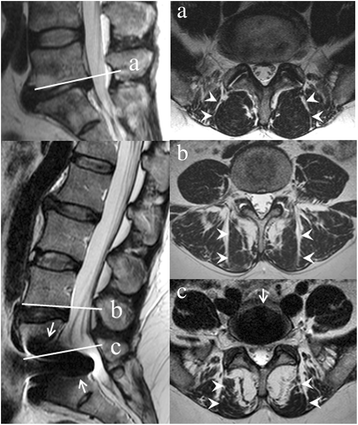

Methods: The study is secondary analysis of data from a trial with 2-year follow-up of patients with chronic low back pain (LBP) and degenerative disc randomized to TDR surgery or multidisciplinary rehabilitation. We analyzed (aim 1) patients with both magnetic resonance imaging (MRI) at pre-treatment and valid data on outcome measures at 2-year follow-up (predictor analysis), and (aim 2) patients with MRI at both pre-treatment and 2-year follow-up. Outcome measures were visual analogue scale (VAS) for LBP, Oswestry Disability Index (ODI), work status and muscle fat infiltration on MRI. Patients with pre-treatment MRI and 2-year outcome data on VAS for LBP (n = 144), ODI (n = 147), and work status (n = 137) were analyzed for prediction purposes. At 2-year follow-up, 126 patients had another MRI scan, and change in muscle fat infiltration was compared between the two treatment groups. Three radiologists visually quantified multifidus muscle fat in the three lower lumbar levels on MRI as <20% (grade 0), 20-50% (grade 1), or >50% (grade 2) of the muscle cross-section containing fat. Regression analysis and a mid-P exact test were carried out.